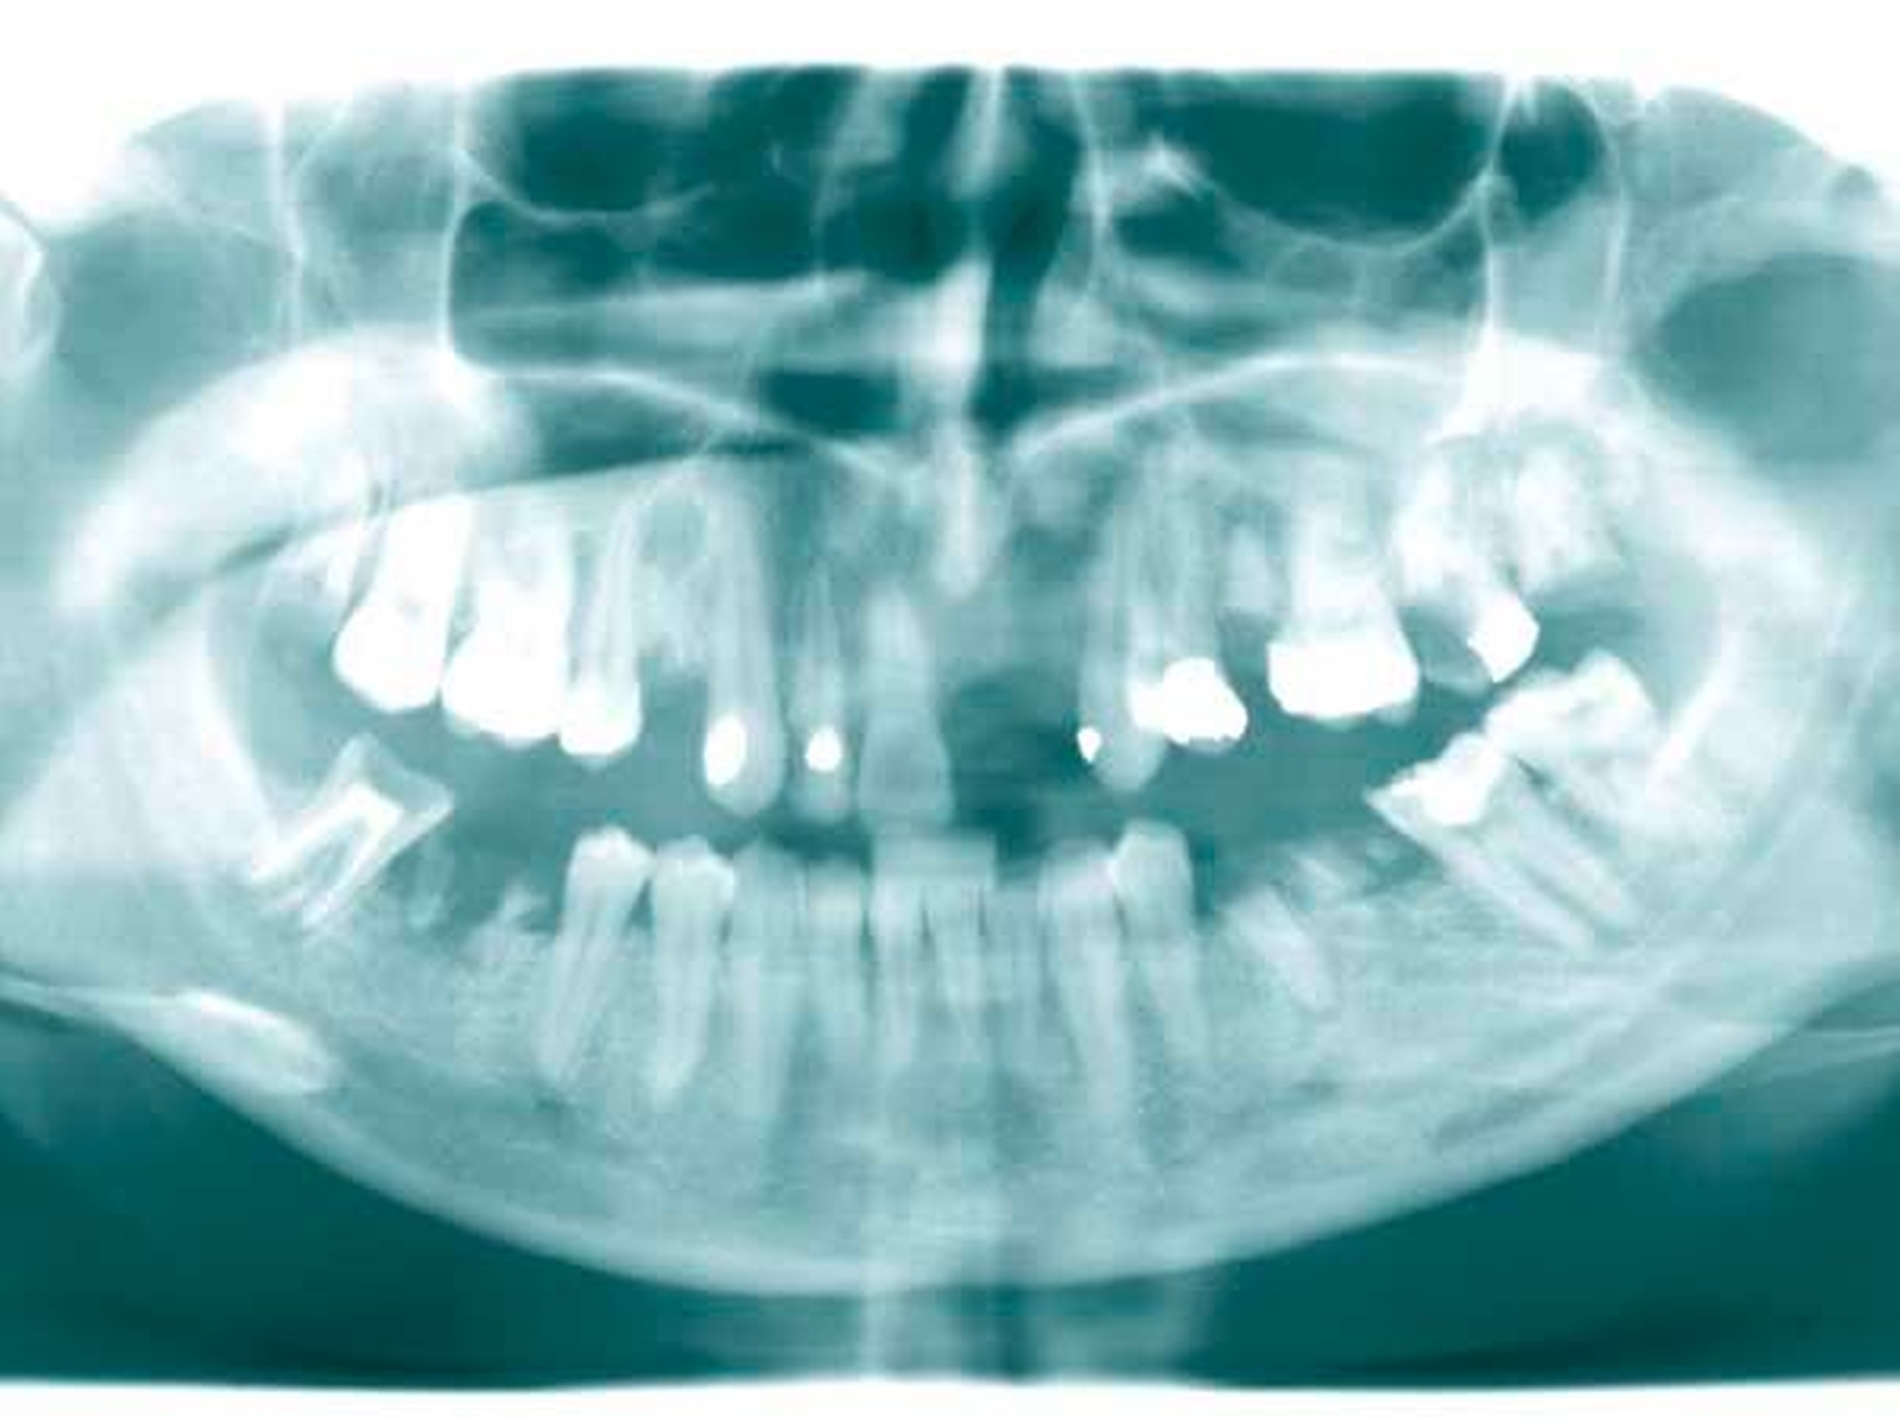

Patientenfall 1

Das Orthopantomogramm (Abbildung 1) zeigt die desolate Gebisssituation einer 31-jährigen Patientin mit ansonsten unauffälliger Anamnese. Die Patientin wurde nach Abschluss der Extraktionstherapie zur prothetischen Beratung und Weiterbehandlung an unsere Poliklinik überwiesen.

Im Oberkiefer gestattete die Lückengebisstopografie festsitzenden Zahnersatz gemäß den Richtlinien der gesetzlichen Krankenkassen. Im Unterkiefer verblieb nach Extraktion ein karies- und füllungsfreies anteriores Restgebiss von 34 nach 45 (Abbildung 2). Versorgungen mit implantatgestütztem Zahnersatz oder kombiniert festsitzend-herausnehmbarem Zahnersatz schieden aus Kostengründen aus. Angesichts der normalerweise sichtbaren Gussklammer-Verankerungen an den Prämolaren fürchtete die junge Frau eine Demaskierung als Prothesenträgerin.